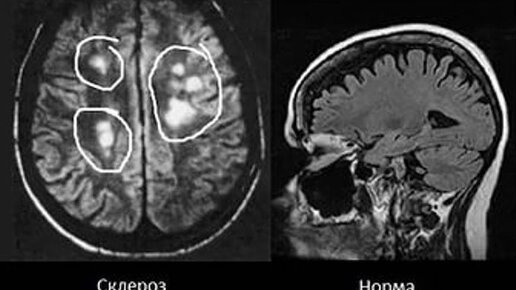

Рассеянный склероз на МРТ головного мозга

Рассеянный склероз представляет собой тяжелое прогрессирующее заболевание нервной системы человека, во время которого больной постепенно теряет двигательные функции и речь. Диагностика рассеянного склероза...

Рассеянный склероз — заболевание, при котором иммунная система атакует ткани головного и спинного мозга. По статистике чаще всего встречается у взрослых людей молодого и среднего возраста. За этот год к нам приехало два пациента с подозрением и подтвержденным диагнозом рассеянный склероз — молодые мужчины в возрасте 20 и 24 лет. Их истории стали основой для этой статьи, где мы расскажем, как проявляется заболевание, в чем заключается опасность, если вовремя не остановить течение болезни; как диагностировать и лечить рассеянный склероз...